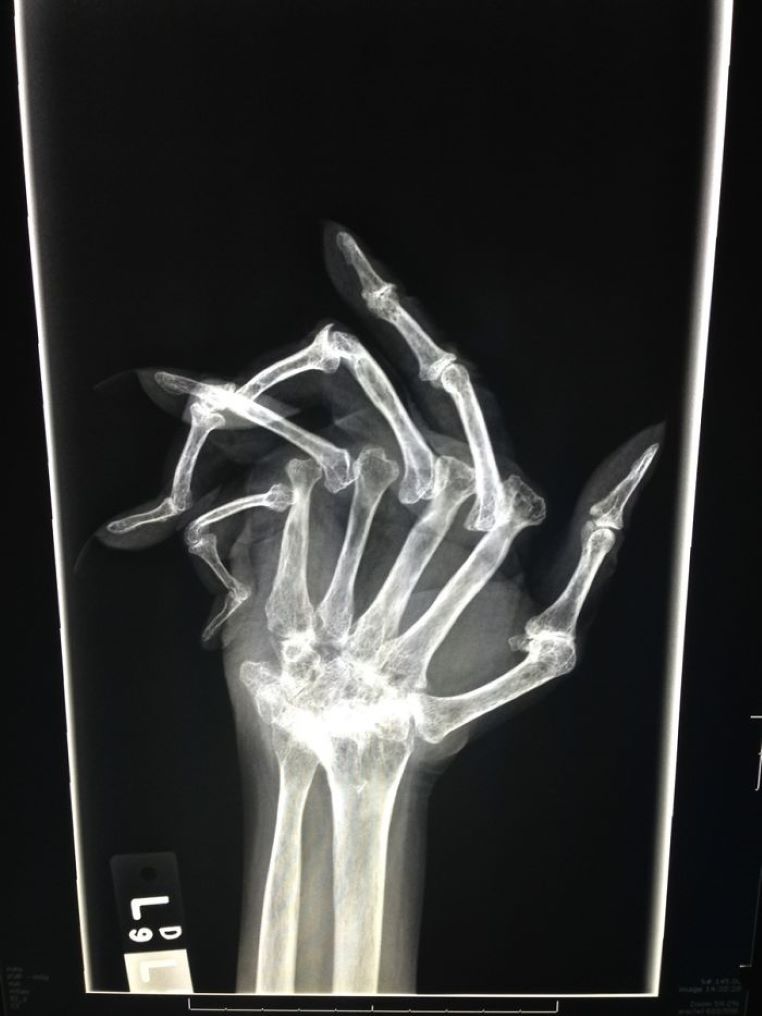

Une personne atteinte d’une polyarthrite rhumatoïde avancée, passe une radio

galerie-rayon-x-doigts